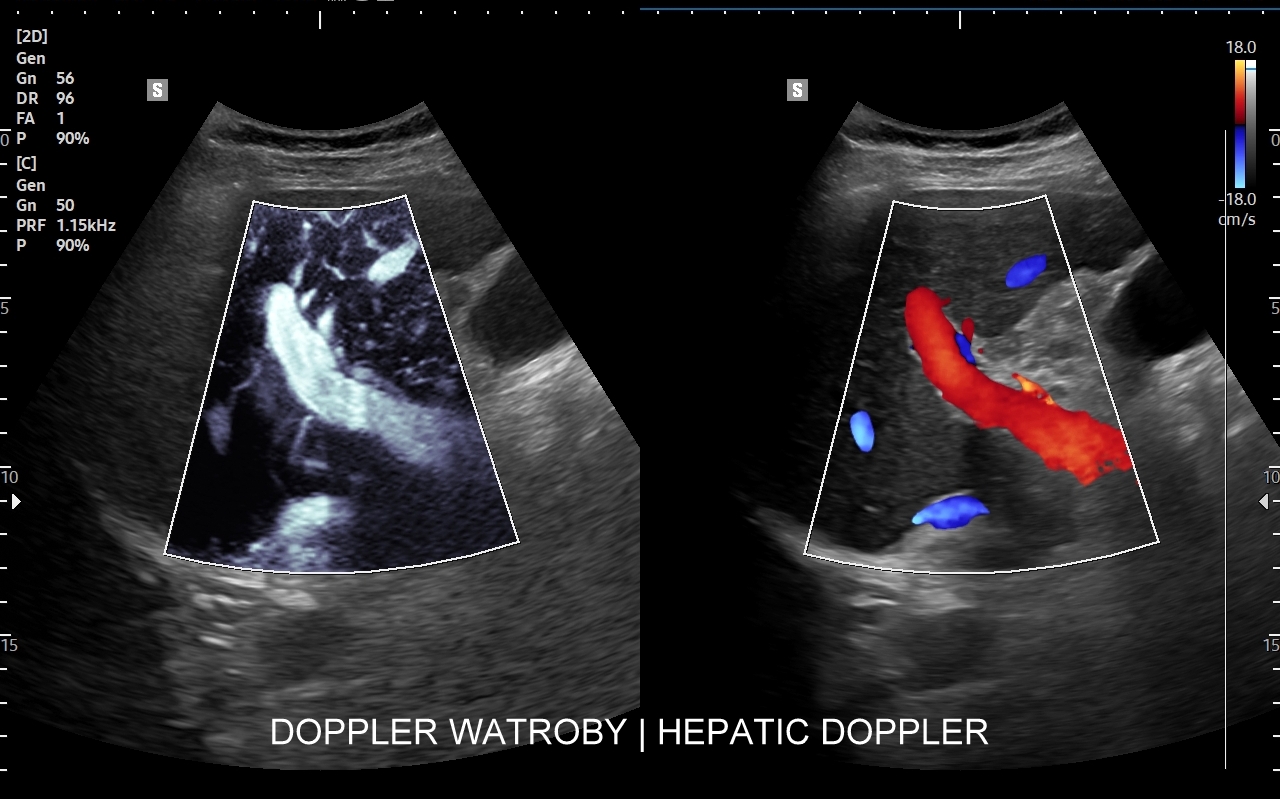

Wątroba posiada unaczynienie różnego typu, a każde o swojej indywidualnej charakterystyce. Są to unaczynienie tętnicze, unaczynienie wrotne (żyła wrotna i jej dopływy z narządów jamy brzusznej), odpływ żylny poprzez żyły wątrobowe. W USG Doppler przepływów wątrobowych bada się każdy z tych układów.

Badanie USG Doppler układu wrotnego wątroby łącznie ze standardową oceną morfologii wątroby i śledziony wykonywane jest najczęściej w ramach diagnostyki nadciśnienia wrotnego, czyli podwyższonego ciśnienia krwi w żyle wrotnej, które może być przyczyną zagrażających życiu żylaków przełyku. Badanie dopplerowskie wątroby uzupełnia również diagnostykę marskości wątroby oraz służy wykrywaniu takich patologii jak zakrzepica w żyle wrotnej i jej dopływach, zakrzepica w żyłach wątrobowych, czy rozprzestrzeniające się nowotwory w naczyniach wątroby.